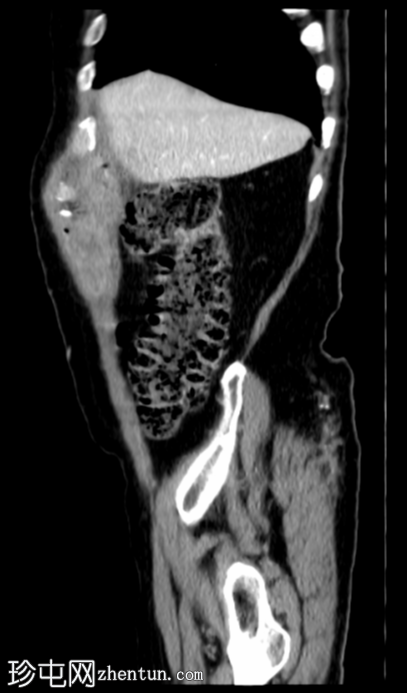

3.png

轴位增强扫描

门静脉期

胆囊底部可见一枚较大的(3厘米)高密度结石,胆囊壁增厚并强化,主要位于胆囊底部。胆囊壁可见一小穿孔,感染扩散至胆囊外,并在肝下区可见气体腔。感染进一步扩散至腹壁肌肉,腹壁肌肉内可见脓肿,边缘强化明显,囊性坏死中心,腔内可见气体腔。十二指肠第一段与炎症胆囊粘连。

检查结果提示急性胆囊炎合并腹壁脓肿。

右侧膀胱有两个小憩室。